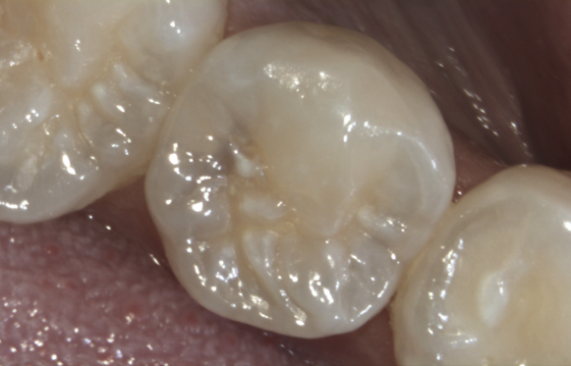

Befund: versteckte Zwischenraum-Caries am Backenzahn

unsichtbare<br />

Zwischenraum-Caries

unsichtbare

Fertig: Die ästhetische Kompositfüllung!